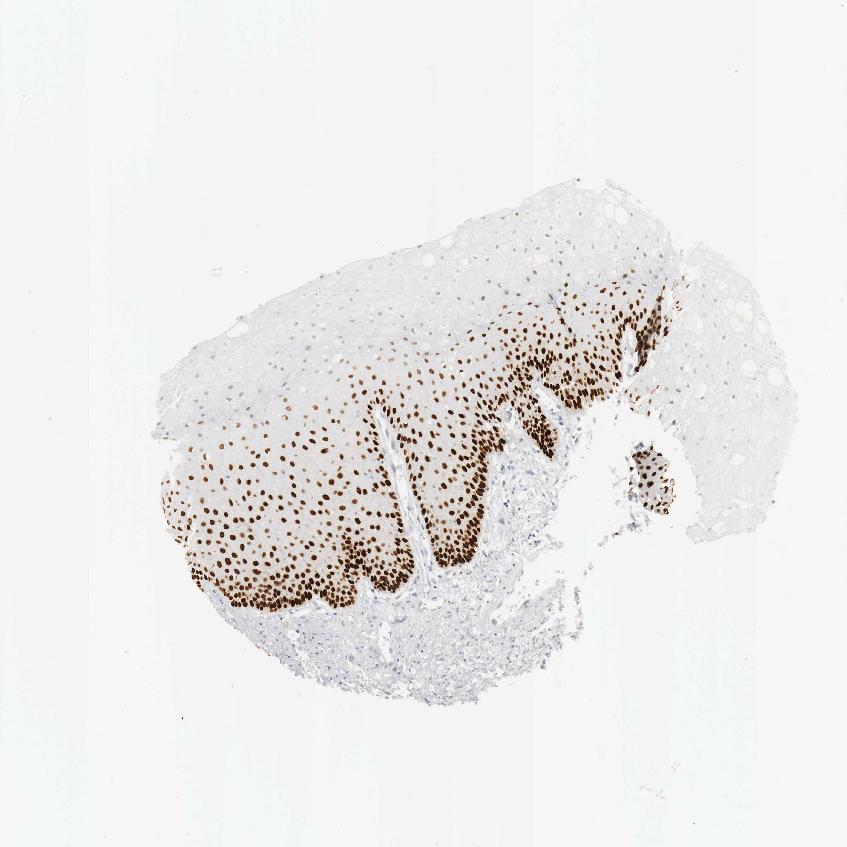

TISSUE PRIMARY DATA ORAL MUCOSA Show tissue menu

Oral mucosa

ORAL MUCOSA - Antibody stainingi

Antibody staining in the annotated cell types in the current human tissue is reported as not detected, low, medium, or high, based on conventional immunohistochemistry profiling in selected tissues. This score is based on the combination of the staining intensity and fraction of stained cells.

Each image is clickable and will lead to virtual microscopy that enables deeper exploration of all samples and also displays staining intensity scores, fraction scores and subcellular localization as well as patient and tissue information for each sample.

Antibody HPA006288Antibody HPA007010Antibody CAB000083

Squamous epithelial cells HighHighHigh